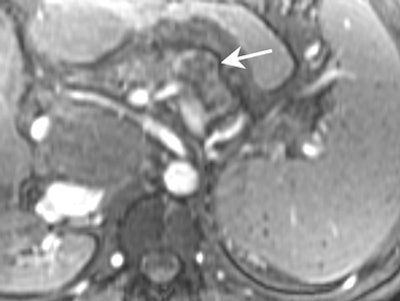

![]() |

| MRI demonstrating mucinous cystadenoma in tail of pancreas (arrow). On T2-weighted images the cyst fluid has high signal intensity similar to CSF. |